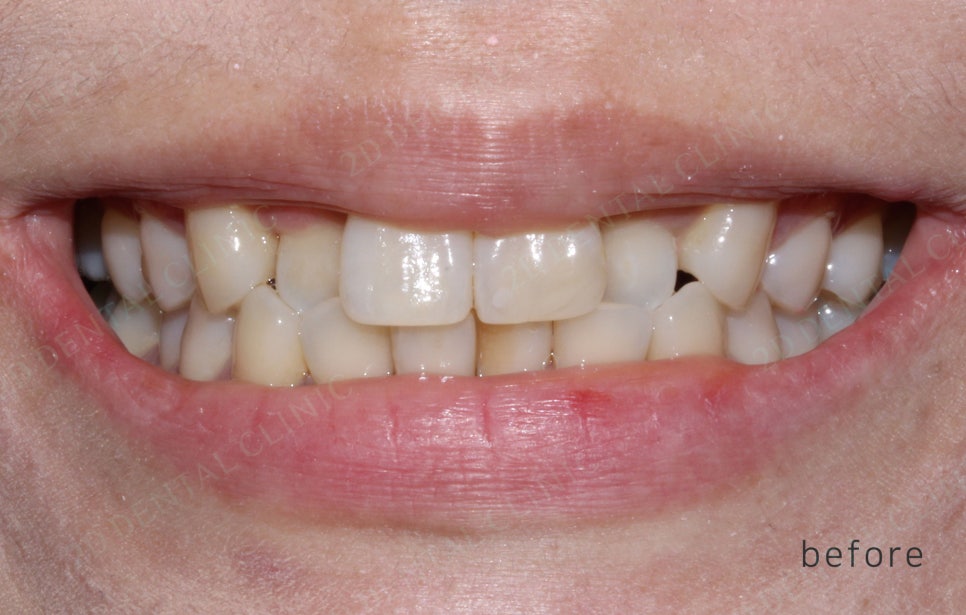

2D(투디)교정 앞니덧니,반대교합 치아교정

환자분이 2D치과(투디치과)에 방문했을때,

드라큘라같은 덧니 치아때문에

너무 스트레스 받아요

교정을 하고싶은데 교정기간이

부담이 돼요...

라며 환자분께서 말씀해주셨어요:)

"측절치 반대교합"이 주된 문제에요.

하지만 전화 상으로는 눈에 보이는

치아의 상태, 간단히 얘기하면

앞니 덧니, 송곳니 덧니가 있어요.

-Tx plan-

CC: 앞니 덧니

상악 6전치/하악6전치

투디교정장치

치간삭제(IPR)

상악 제1대구치에 Bite raise(일시적)

이번 앞니 덧니 케이스는

송곳니 교합이 매우 양호하고 비대칭도 없었어요

그래서 "투디교정"으로 결정!!

<교정 전/후 >